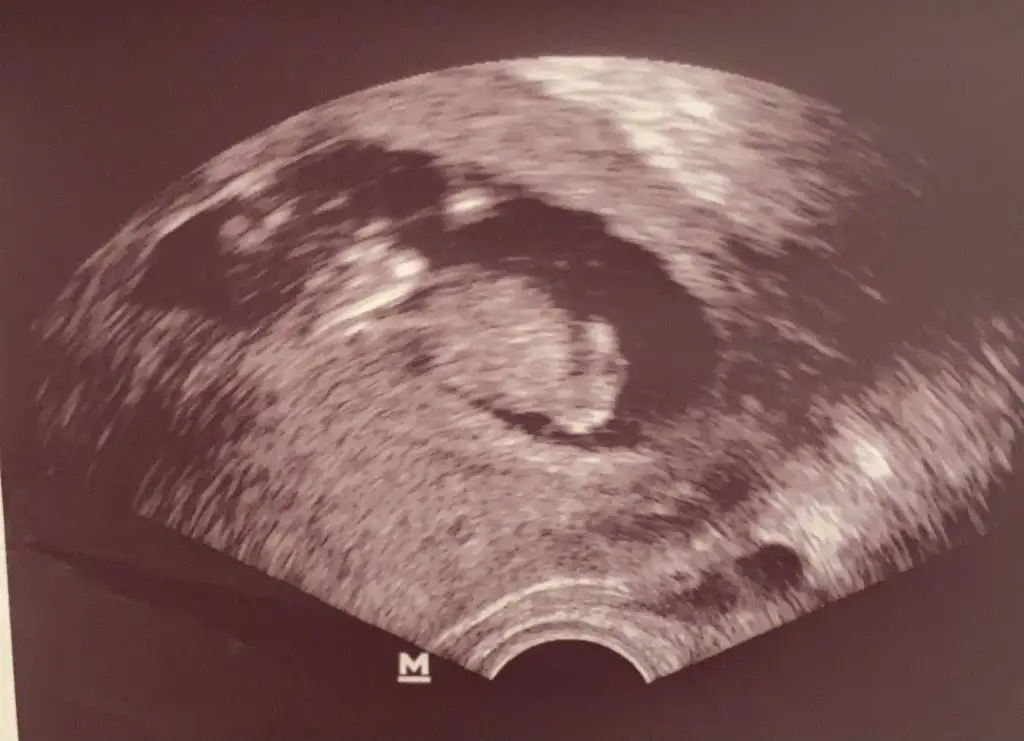

Sağol canım Allah razı olsun. Benim bebekte yüz üstü duruyordu sonra döndü falan ama yine yüzüstü pozisyon aldı. Bi ara bu konuda geçmişti burda. Bacaklarıni açık halde yakaladı doktor gösterdi ama onun görüntüsünü vermemiş.Gözün aydın canım rabbim kucağına almayı nasip etsinUsg var mı

Evet canımSağol canım Allah razı olsun. Benim bebekte yüz üstü duruyordu sonra döndü falan ama yine yüzüstü pozisyon aldı. Bi ara bu konuda geçmişti burda. Bacaklarıni açık halde yakaladı doktor gösterdi ama onun görüntüsünü vermemiş.

Ben o konuyu okudum ama şöyle soyleyim kesinlikle yanlış benim kiz hep ters duruyor ama kiz

Bnmde kız hep yüzüstü duruyor doktor çevirmeye calisti baya sonrada poposunu döndü bizeBen o konuyu okudum ama şöyle soyleyim kesinlikle yanlış benim kiz hep ters duruyor ama kiz